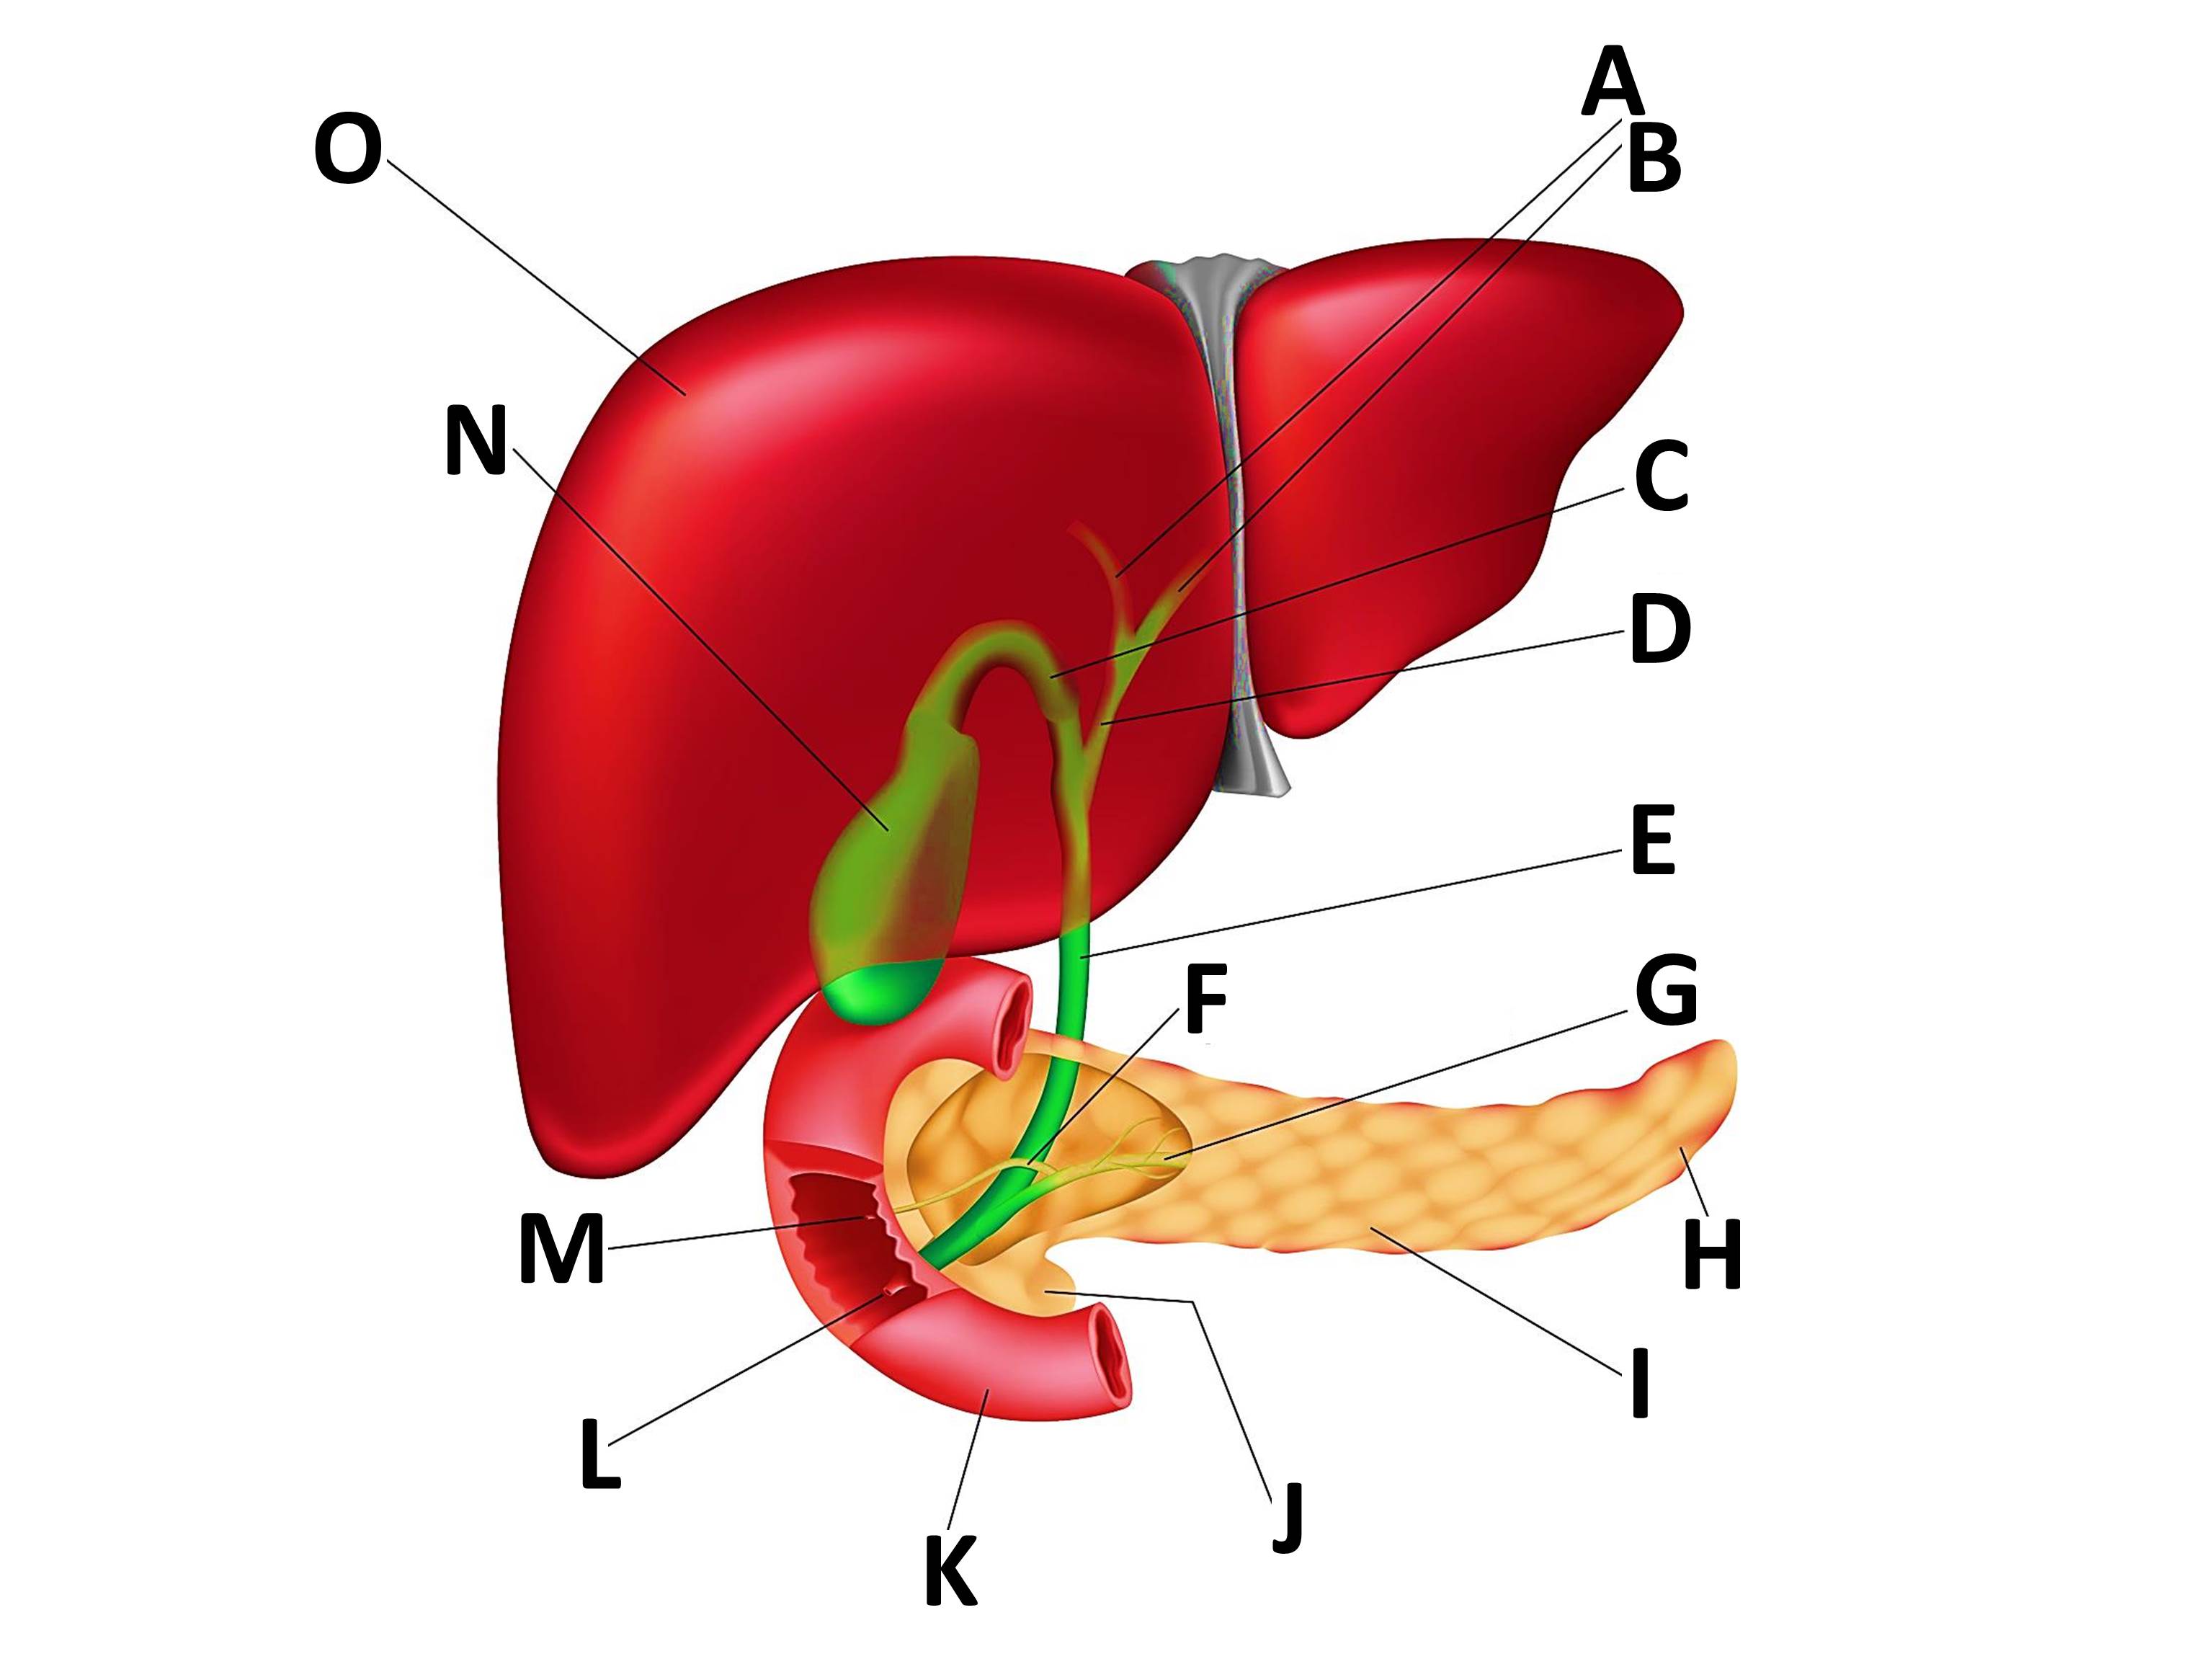

Печень, один из самых крупных и важных органов человеческого тела, выполняет множество жизненно необходимых функций, включая фильтрацию токсинов и производство жизненно важных белков. В данной статье мы рассмотрим, как наглядные изображения печени могут помочь лучше понять её структуру, функции и возможные заболевания. Использование рисунков и диаграмм делает сложные биологические процессы более доступными для понимания, особенно важно это для студентов, врачей и пациентов, стремящихся глубже изучить этот ключевой орган.

Печень рисунок